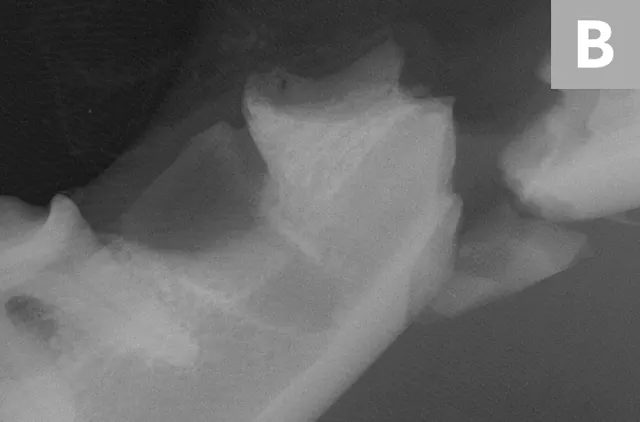

A complete oral examination confirmed stage 4 periodontal disease of numerous teeth (ie, first through fourth maxillary premolars, all maxillary molars, both maxillary canines, all remaining incisors). Dental radiographs confirmed bilateral mandibular fractures at the mesial root of the right mandibular first molar and distal root of the left mandibular first molar (Figures 1 and 2).

Preoperative intraoral dental radiographs of the right (A and B) and left (C) mandibular first molars. There is marked alveolar bone loss secondary to periodontal disease (blue lines), as well as pathologic, iatrogenic mandibular fractures (arrows).